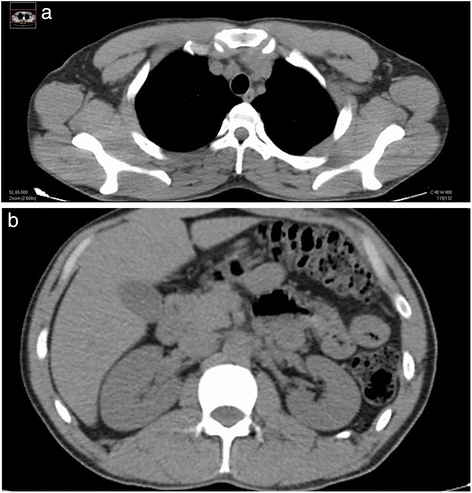

Surgical complete debridement of the necrotic burned tissues were performed soon after admission of the patient and cell therapy applied immediately (Fig. 2). Probably due to some potential yet unknown properties of MSCs or any of its transportation materials, or by the simultaneous use of the polymeric transparent film as a dressing, lost of plasma was not a concern, necrotic tissues were not ever seen again after escharotomy at any site, and good blood supply without wound infection was always present after application of the stem cells (Fig. 3a). Bacteriological analysis of the wound surfaces and clinical observation did not show evidence of local infection at any time. Burn wounds were only washed with warm water and soap at the end of the first week after the cell treatment and every third or fourth day later on, always covering the lesions with the polymeric film. Antiseptics were not used at any time. The transparent film dressing did not ever stick to the wounded areas, and a yellowish fibrinoid material was always present and seen under it (Fig. 3f). Besides this observation, other exudates were minimun under our film not needing any special drainage. An increasing progressive development of new capillaries were soon observed in the surface of all treated wounds. A “granulation tissue-like” appearance was evident in all the wounds by the fifth day, and from this moment, “hyper-granulation” also developed and persisted on all treated burn wounds (Fig. 3a–f). There was a fast and significant improvement of the clinical condition of the patient, and pain in the burned areas decreased in intensity. A surprisingly early and not very well adherent thin epithelial growth was seen rapidly advancing from the wound edges in relation with the topical cell therapy, but the “granulation-like” wound surface remained almost unchanged in the center (Fig. 4a–b). After 35 days of treatment with two courses of CMSCs application as described, the complete epithelialization of the wounds seemed to be too slow to be waited further. Then, after superficial surgical shaving of all the “hyper-granulating” areas, AMSG was applied. Skin grafts were obtained from the non-burned zones, meshed and used to cover the wound surfaces on every site. About 50 % of the remaining wound surface was covered during a first operation, and additional transplantation of more auto-grafts were done after another week always using the polymeric film as a dressing. All AMSGs permanently adhered to the wounded surfaces and were always viable. Interestingly, the spaces inside the meshes seemed to rapidly and completely epithelialized in a very short period of time. The patient keeps continuously improving day after day, leaving the bed and starting walking and moving with significant freedom. He was finally discharged from the hospital in a very well satisfactory condition for outpatient rehabilitation and follow-up (Fig. 5a–f). More interesting is the fact that in the sites in which AMSGs were applied, a slowly progressive integration of the grafts with disappearance of their meshed aspect seems to be taking place, looking more like normal skin. Almost no retraction is seen at any site, and the deep dermis as well as the epidermis seem to be normal again as observed in CT scan studies (Fig. 6a–b).